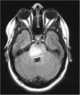

Pontine glioma